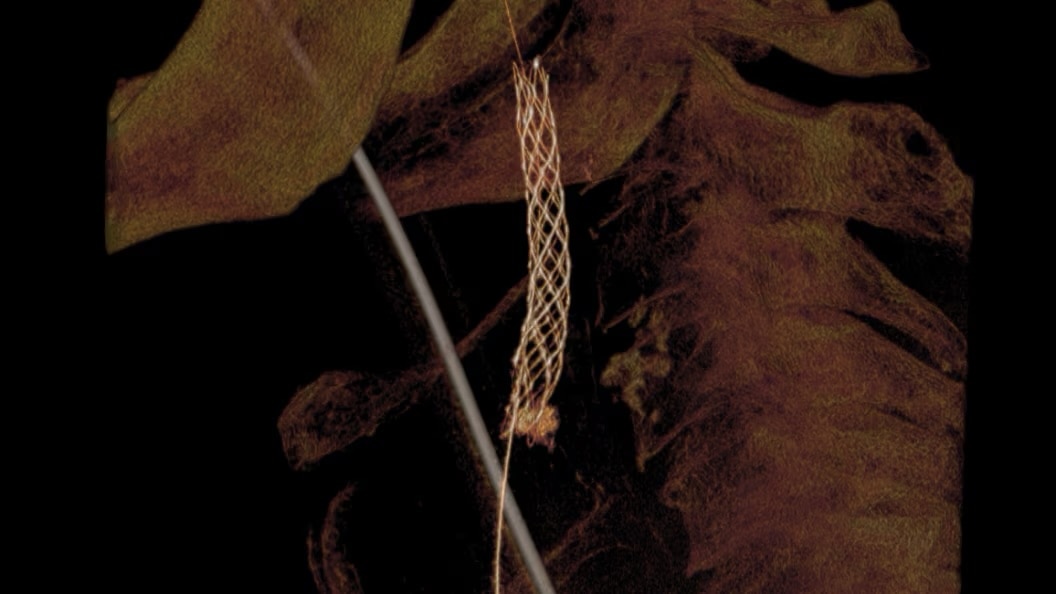

Cone-Beam Computed Tomography

Experience the precision of cone-beam CT, offering high-resolution 3D imaging for accurate diagnostics and treatment planning with enhanced safety and efficiency.